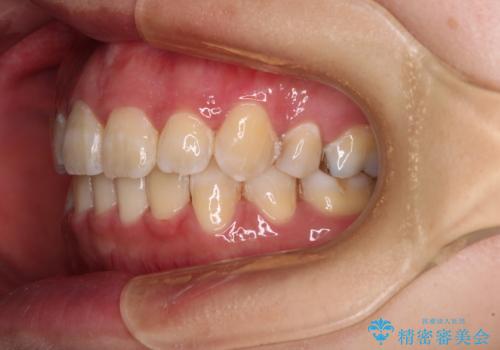

スペースを閉じるステージでの移動がとても早く、1年半ほどで終えることができました。

唇が引っかかる感触もなくなり、口が閉じやすくなりました。